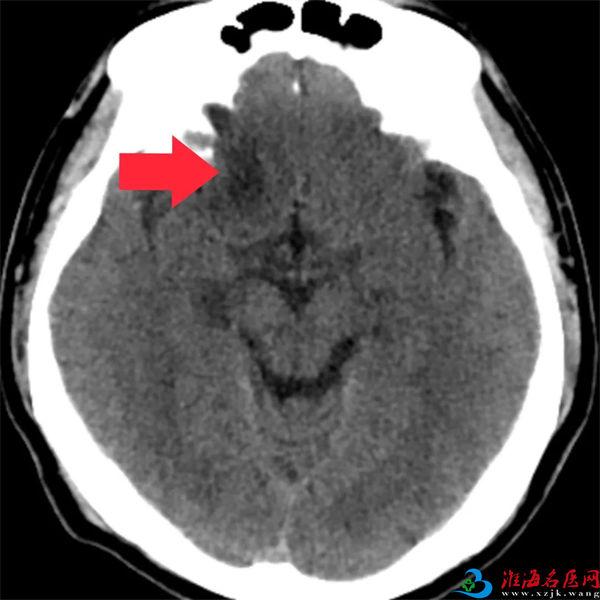

老家安徽的W先生(化姓)今年57岁,8个月前在外院体检时,意外发现自己右额叶有斑片状低密度病灶,性质不明。半个月前,他又在外院进行头颅磁共振及增强扫描、波谱分析等检查,提示右额叶占位。

术前患者的CT和磁共振影像

既然是占位,一般考虑为肿瘤,究竟是原发性肿瘤还是转移瘤,还需进一步检查。诊疗结果让W先生意识到自己这次得的不是小病,慎重起见,多方打听后,他慕名来到徐州一院,找到神经肿瘤专家张继东寻求进一步诊治。